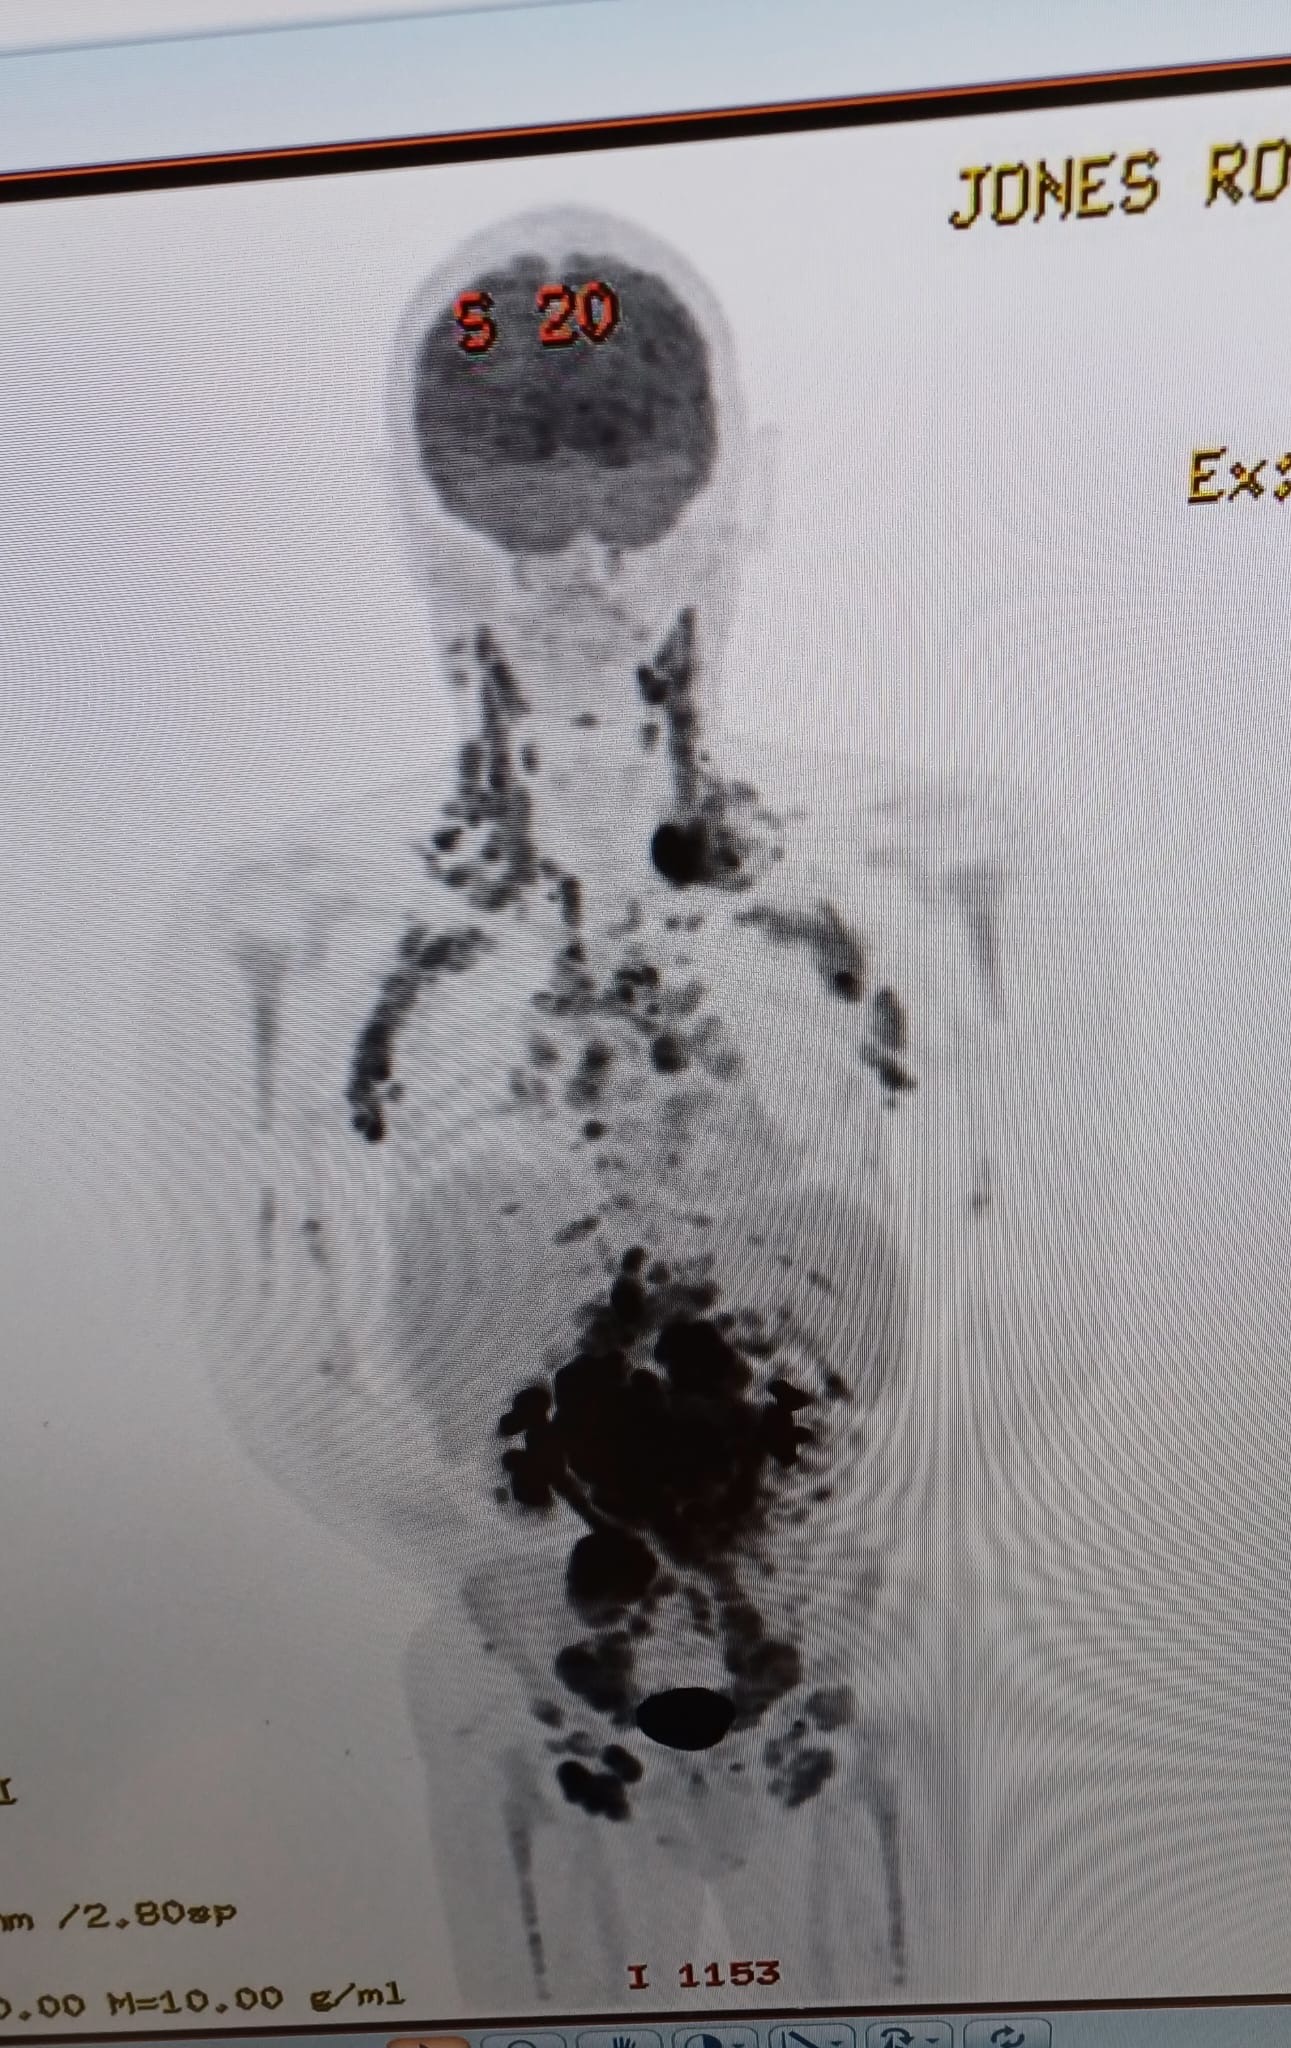

In April of 2024 we were devastated to receive Roy’s diagnosis of Non-Hodgkins Lymphoma, he battled through 6 gruelling rounds of chemotherapy and 15 of radiotherapy, he lost over 4 stone in weight and every single hair off his body this as you can imagine really took a toll on his confidence.

The Cancer has returned with a vengeance.